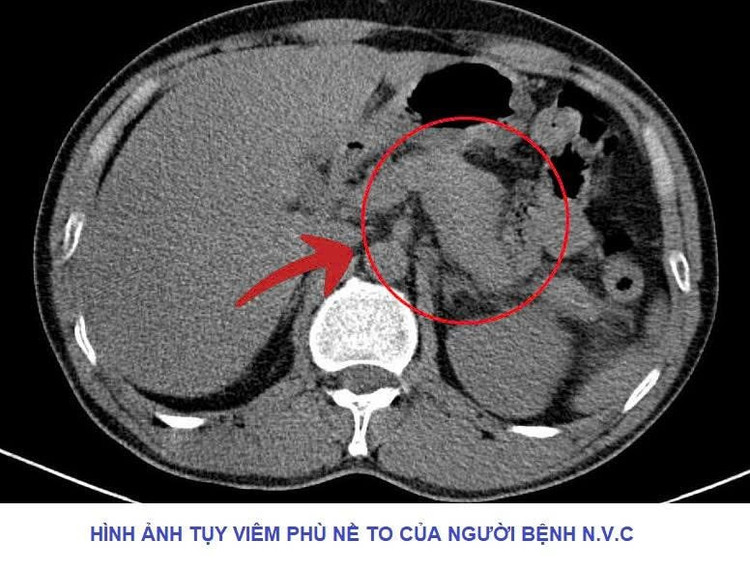

Theo đó, Khoa Cấp cứu tiếp nhận người bệnh N.V.C (47 tuổi, trú tại tỉnh Phú Thọ), nhập viện trong tình trạng đau bụng dữ dội vùng thượng vị, buồn nôn, bụng chướng nhiều… và được chẩn đoán viêm tụy cấp. Đáng chú ý, từ năm 2020 đến nay, người bệnh có thói quen uống rượu mỗi ngày từ 300-500ml.

Sau khi bác sĩ tiến hành thăm khám, thực hiện các cận lâm sàng cần thiết, kết quả cho thấy tuyến tụy to, có thâm nhiễm viêm, chỉ số men Amylase vượt ngưỡng rất cao. Các bác sĩ nhanh chóng hội chẩn và xác định người bệnh mắc viêm tụy cấp, chỉ định đặt sonde dạ dày và đặt đường truyền tĩnh mạch trung tâm.